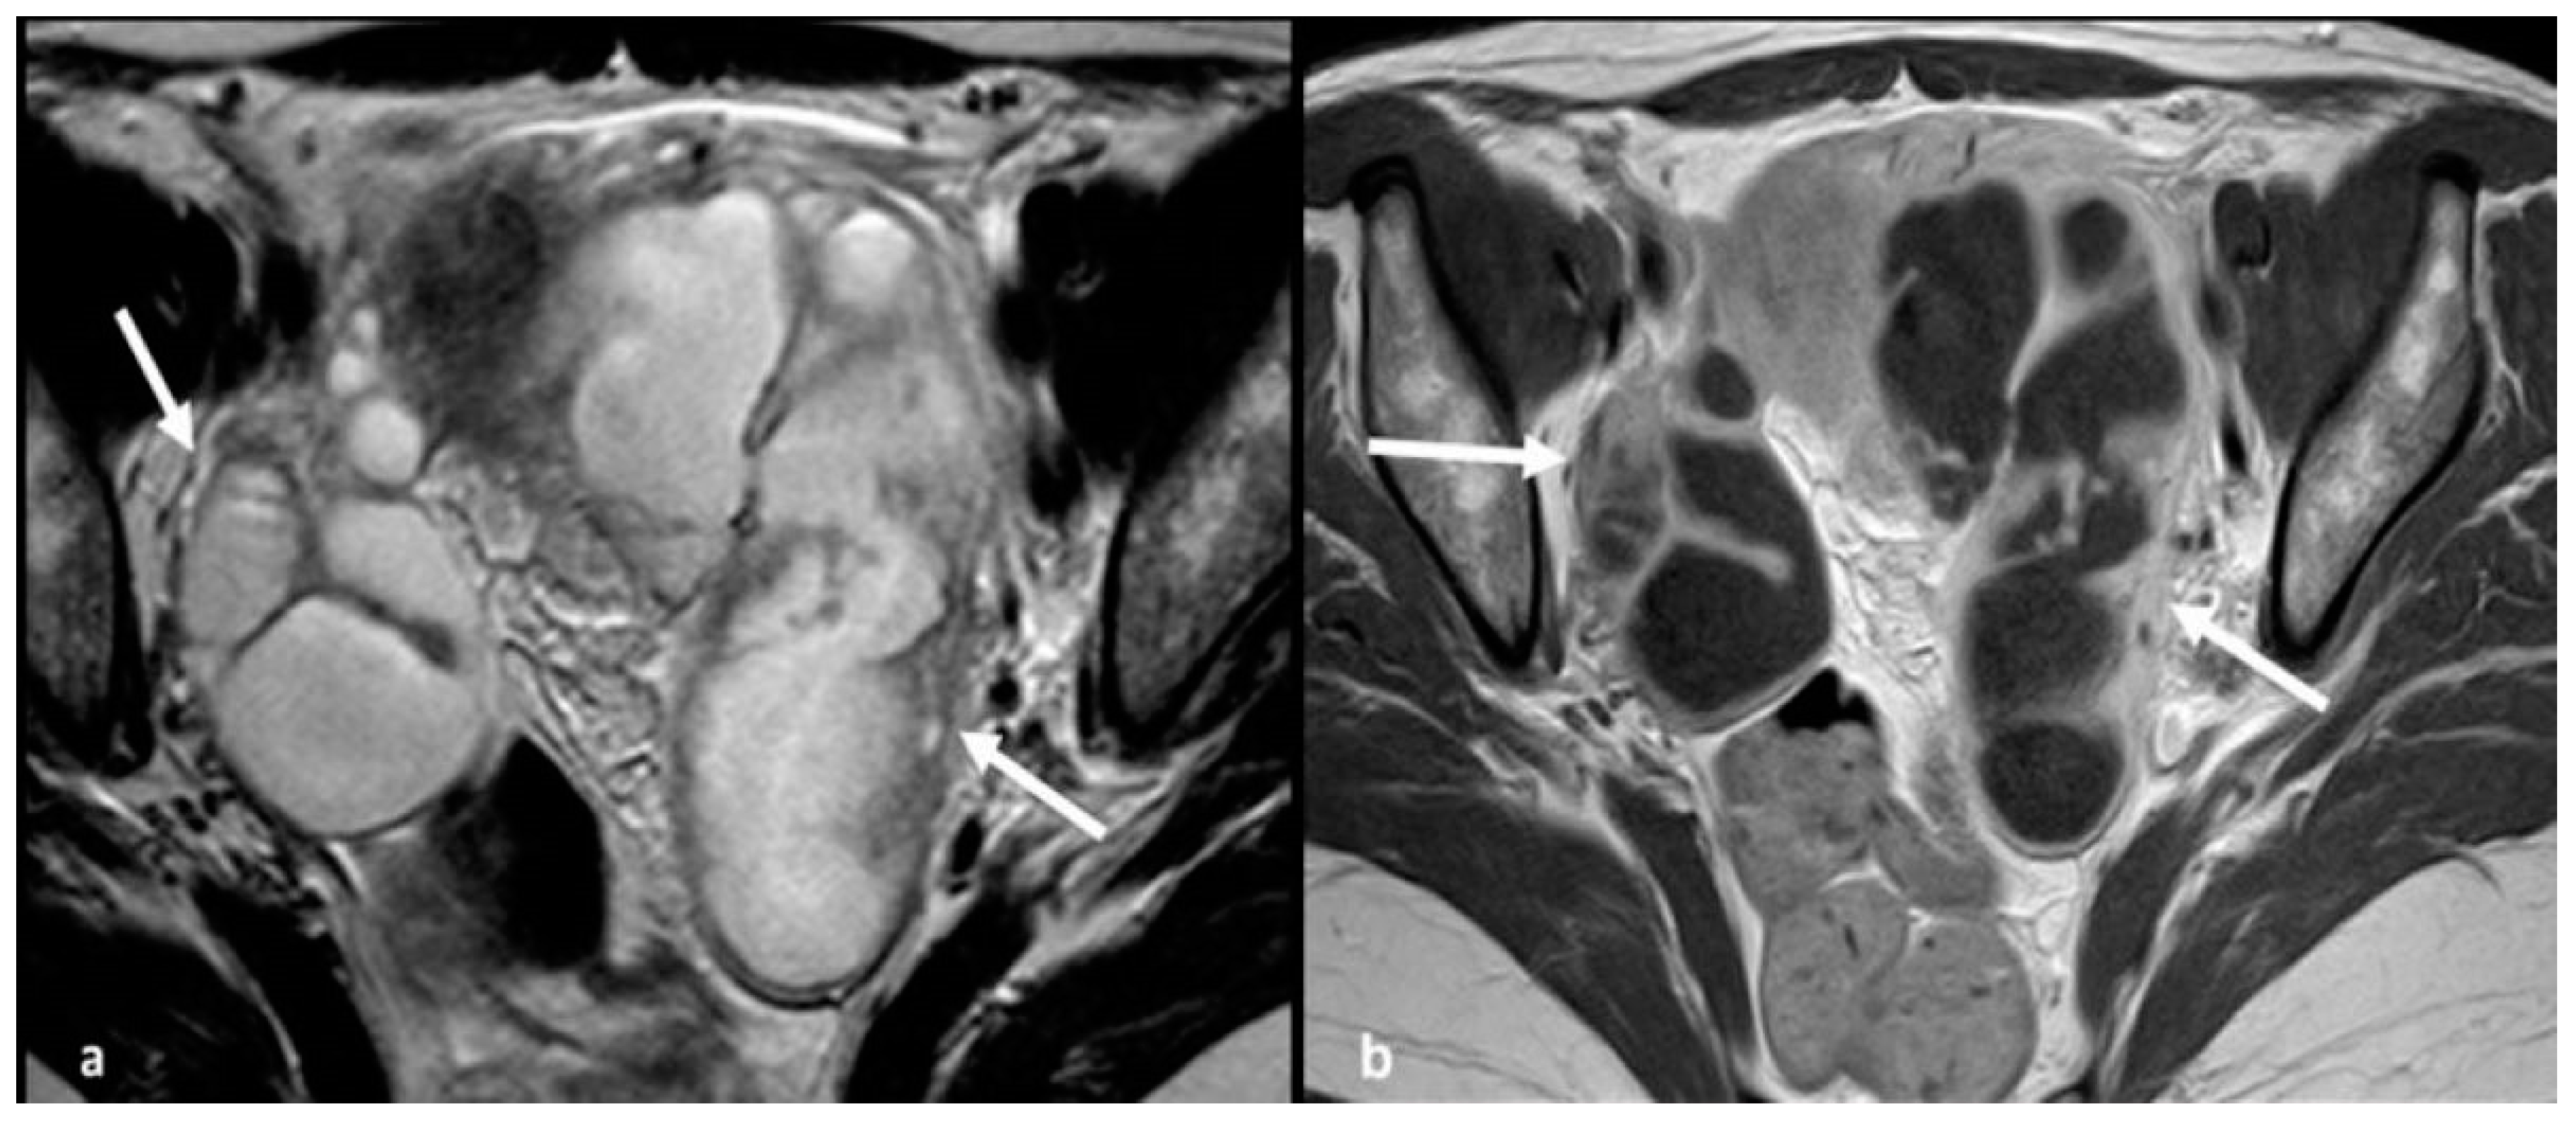

2.1.3. Mucinous Borderline Neoplasms and Mucinous Cystadenocarcinoma

2.1.4. Endometrioid Carcinoma and Clear Cell Carcinoma